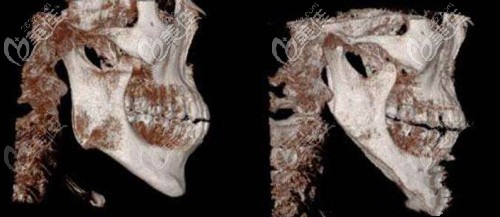

你知道做下颌角切除手术前要进行3项体检还要拍片吗?

下颌角切除手术可被划分为3级整形手术,所以术前一定要认真对待,医院会给你进行两项体检,还要拍片设计方案。